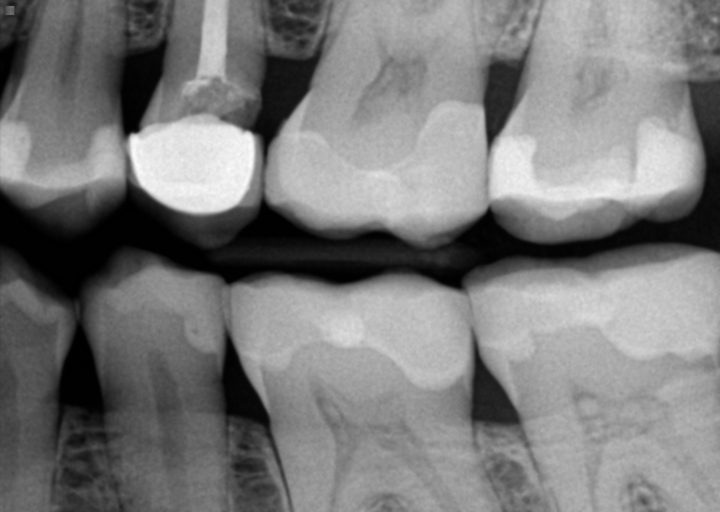

Cavity in tooth with root canal

Iam 72 and have had a tooth with a root canal covered with silver filling for years. Yesterday the dentist found a small cavity in the silver. He said that nowadays the root canals are covered with a crown and I should get a crown before the cavity gets larger. The cost for the crown is a real financial burden for me as I am retired and on a fixed income. Do I need to have a crown to repair this cavity or can I ask the dentist to do something else? Also, since this is a small cavity (the hygienest who cleaned my teeth never saw it) is it possible that it can go without being filled?

There is no way to tell how large the cavity is under the silver filing without completely removing it. The dental instrument may fit into a small area to detect the decay, which could travel deep into the tooth. Recurrent decay will compromise the tooth and with an existing root canal you are at risk of it fracturing. Being on a fixed income can present a problem, however if the tooth fractures and needs to be extracted, it can also be costly. Meet with the office financial coordinator and ask about affordable payment options that will fit into your monthly budget. Most offices offer interest free payments in order to assist their fixed income patients.